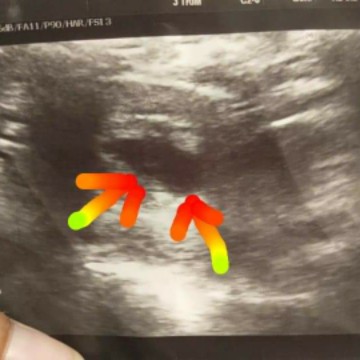

มีแม่ๆพ่อๆคนไหนเห็น กลมๆ2จุดเหมือนเราบ้างคะ แม่บ้านนี้ไม่มั่นใจว่าเห็นคนเดียวหรือป่าว